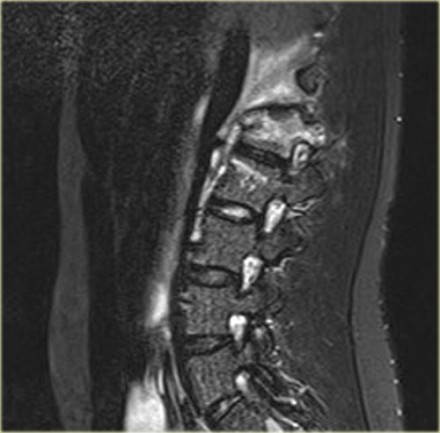

Here is a patient with distraction on the anterior side.

Notice the rigid spine and how easily this major injury can be overlooked.

This patient had a motorcycle accident.

The MRI demonstrates rupture of the flava ligaments, interspinous and supraspinous ligaments as well as fracture of the posterior elements and compression of the vertebral body.

A posterior spondylodesis was performed.